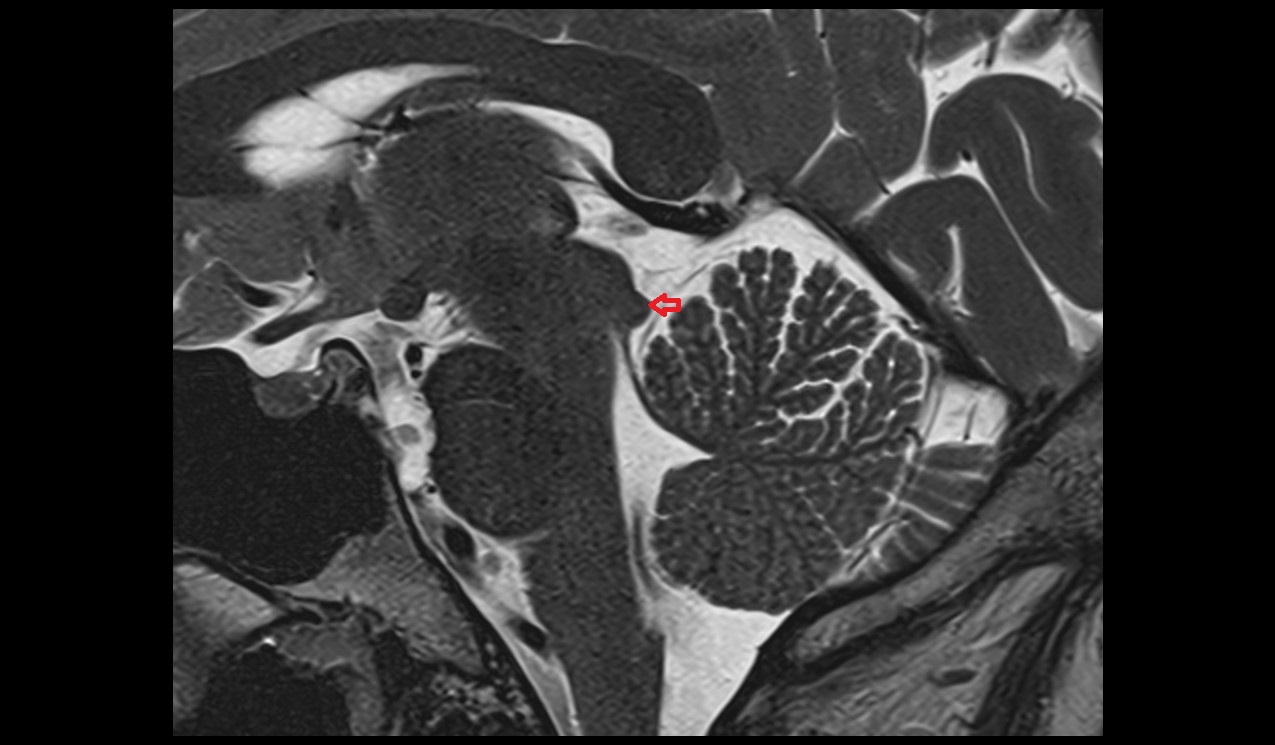

- Arbor Vitae (Cerebellar White Matter)

- White matter of cerebellum (Arbor vitae)

- Hippocampus

- Body of hippocampus

- Head of hippocampus

- Tail of hippocampus